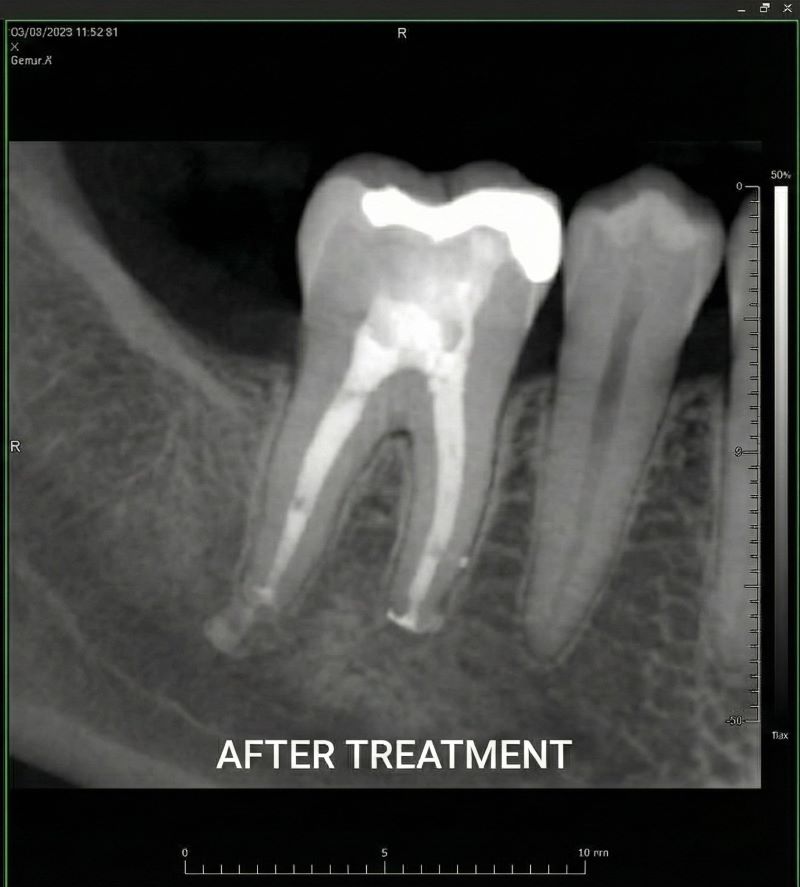

Our endodontic dentists use rotary instruments, digital imaging and microscope-assisted techniques to deliver precise, comfortable care. We also provide retreatment and apicoectomy for complex cases where a previous root canal has failed. By preserving your natural tooth whenever possible, endodontic care often provides a more stable long-term solution than extraction and replacement. Endodontic care includes root canal therapy to treat active infection and retreatment when a previous root canal needs further care to preserve the tooth.

Our endodontic specialists use advanced microscopes and digital imaging to perform precise treatment. Unlike general dentistry, microscopic endodontics helps identify hidden canals and address complex infections while preserving as much natural tooth structure as possible.

Under local anaesthetic, your endodontist makes a small opening in the tooth, removes the infected pulp and cleans and shapes the canals. They then fill the canals with a biocompatible material and seal the tooth. A crown is placed later to restore function.

If a previously treated tooth doesn’t heal properly or becomes reinfected, retreatment can reopen the tooth, remove the old filling material, disinfect the canals and reseal them. This gives the tooth another chance for success.